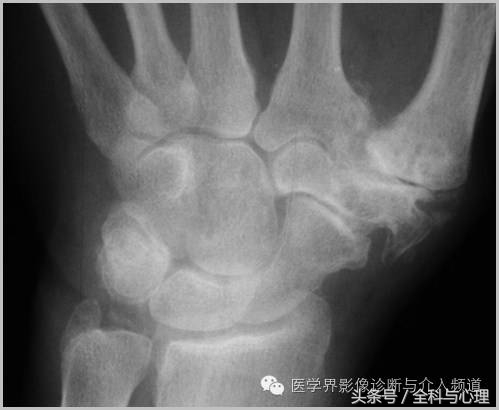

3、CPPD(焦磷酸钙沉积症)相关性钙化

CPPD(焦磷酸钙沉积症)